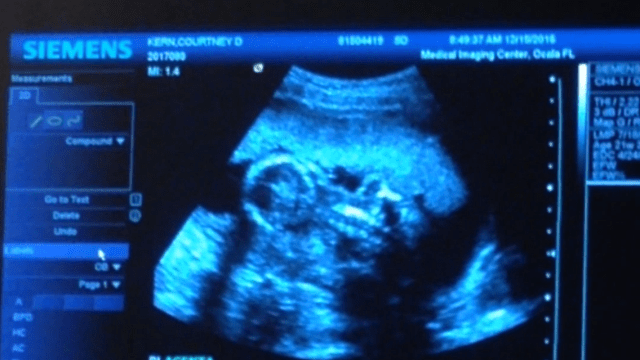

Last week I was privileged to see baby blueberry on the sonogram. It never never never gets old seeing a brand new life. I remember how excited it was so long ago seeing my babies for the first time and this time was no different.

We had planned a gender reveal celebration with the family that night, so fingers crossed BB would allow us to know his/her gender. The radiology technician was not promising.

BB did not disappoint.

Blueberry is a BOY!!!!